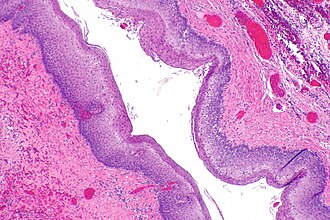

Consistent with Zenker's diverticulum (squamous mucosa). H&E stain. | |

| LM | squamous mucosa without nuclear atypia +/- parakeratosis |

Features:[7]

- Squamous mucosa without nuclear atypia +/- parakeratosis.

ZD - very low mag. (WC)

ZD - low mag. (WC)

ZD - intermed. mag. (WC)

Submitted as "Zenker's Diverticulum", Excision: - Squamous mucosa with parakeratosis, mild chronic inflammation and fibrosis; compatible with Zenker's diverticulum. - NEGATIVE for dysplasia and NEGATIVE for malignancy.